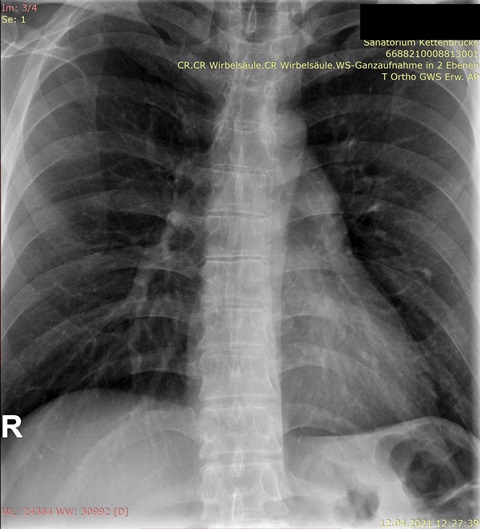

Bei Männern mit "leichter" Skoliose kommt es nicht selten vor, dass ein Rundrücken und Hohlkreuz das eigentliche Problem sein kann. Deshalb braucht man auch immer ein Röntgenbild der gesamten Wirbelsäule von vorn und eins von der Seite, wo man das erkennen kann.

Habe die Bilder. Für mich als Laie sieht es nicht so schlimm aus auf den Röntgenaufnahmen, aber ich bin in der Realität total asymmetrisch und schief, und am extremsten ist, dass die Rippen/Brustkorb auf der rechten Seite viel mehr rausstehen und das optisch sehr auffällt.

Im Anhang die Bilder.

Ich (auch Laie) sehe nur eine geringe Seitabweichung der Wirbelsäule, aber eine deutliche Rotation, erkennbar an den "Kringeln" der Dornfortsätze und Querfortsätze. Ich denke auch, dass da ein Spezialist gefragt ist.rudi777 hat geschrieben: ↑Do, 22.04.2021 - 16:20 Für mich als Laie sieht es nicht so schlimm aus auf den Röntgenaufnahmen, aber ich bin in der Realität total asymmetrisch und schief, und am extremsten ist, dass die Rippen/Brustkorb auf der rechten Seite viel mehr rausstehen und das optisch sehr auffällt.